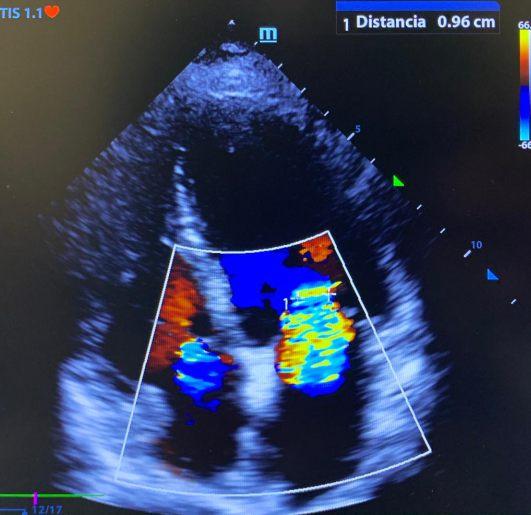

Experto en cateterismo cardíaco, implantes de stents y procedimientos valvulares percutáneos por mínima invasión (sin cirugía abierta) con cer ficaciones internacionales de implantador de válvula aór ca transcatéter (TAVI).

• Implante de válvula aórtica transcatéter (TAVI)

• Remplazo y reparación de la válvula mitral y tricúspide por cateterismo (Clip Mitral y Tricúspide)

• Cierre de Orejuela Izquierda

• Reparación de Fugas Paravalvulares

• Cierre de comunicación interauricular, ventricular y foramen oval

• Cateterismo cardiaco con implante de Stents

• Implante de marcapaso

Egresado del Centro Médico Nacional "La Raza"

Certificado por Consejo Mexicano de Cardiología Céd. Esp. UNAM. 11747036

Experto en diagnóstico, tratamiento y seguimiento de enfermedades cardiovasculares

• Cardiopatía Isquémica

• Infarto del miocardio

• Hipertensión arterial

• Insuficiencia cardiaca

• Arritmias

• Enfermedades de Válvulas cardiacas

• Colesterol y Triglicéridos, entre otros.

Consultorio 910

WhatsApp 9993 95 0990

Urgencias 9811 25 5376

Dr. Russell González Tuyub Cardiología Mérida cardiomerida